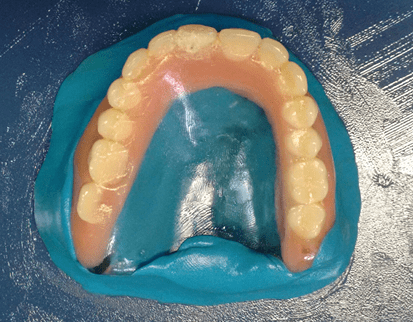

The treatment plan consisted of performing a total superior prosthesis obturator by the cloning technique and the preparation of a conventional removable partial prosthesis (PPR). Cloning of the total superior obturator prosthesis began with the application of solid vaseline on the bench and in the old prosthesis, the condensation silicone (Clonage®, Nova DFL, Brazil) was manipulated to model the inner part of the prosthesis, covering a portion of the outer edge, leaving it expulsive (figure 3).

Figure 3: Mold making.

Then, a thin layer of solid vaseline was inserted into the base already modeled and the cover and copy of the teeth were made (figures 4 and 5). Soon after, a base of the prosthesis was elaborated with acrylic resin (Duralay®, Reliance, USA) by the brush technique introducing the resin in small proportions, because this type of material has less polymerization contraction (figure 6). Then, perforations were made in the posterior region of each side of the cover, in order to fill the mold with wax 7 (figure 7). Where initially the wax was heated to boiling and with the aid of a glass dripper the increments were added by filling the mold completely (figure 8). And, after cooling the wax, the base cover silicone was removed, thus obtaining the properly mentioned cloning of the old prosthesis (figure 9).

Figure 9: Clone of the total obturator prosthesis.